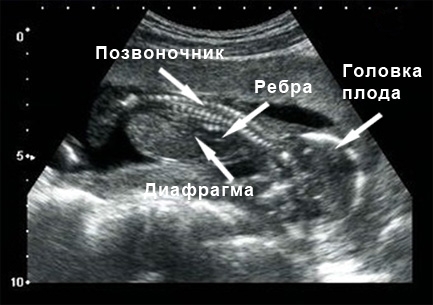

Исследуются ключевые структуры головного мозга плода. В обязательном порядке проводится анализ мозжечка. Нервная система плода практически завершила свой процесс формирования. Оценивается целостность спинного мозга и позвоночника в общем. Будущий ребенок уже хорошо различает время суток.